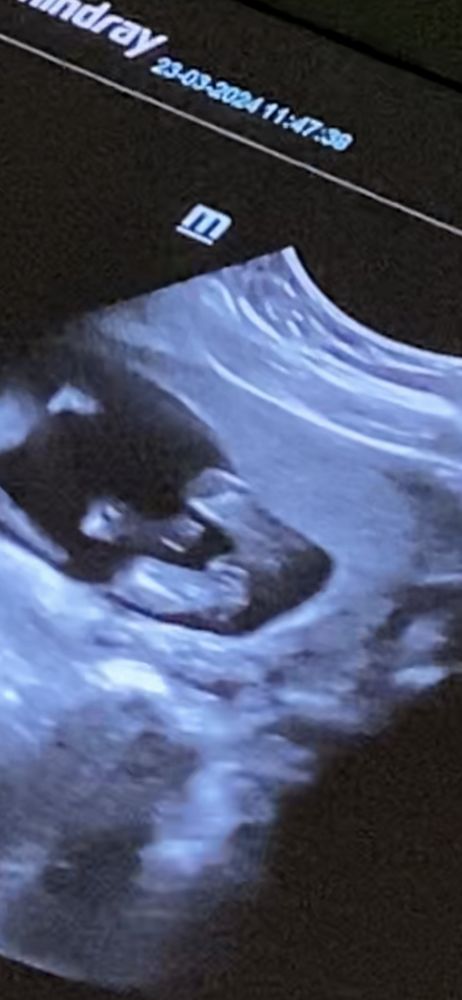

15 недель. Могли ли ошибиться с полом на узи?

Не вижу тут мальчика)) по-моему явная девочка)

Я девочку вижу

Очень похоже на девочку

Есть шанс. В 20 недель точно скажет. Но ошибаются обычно с девочками. Но всё же в 20 скажут тогда уже точно.

Сходите на 3/5 д. Там все отлично видно будет

Мне показалось девочка сразу.